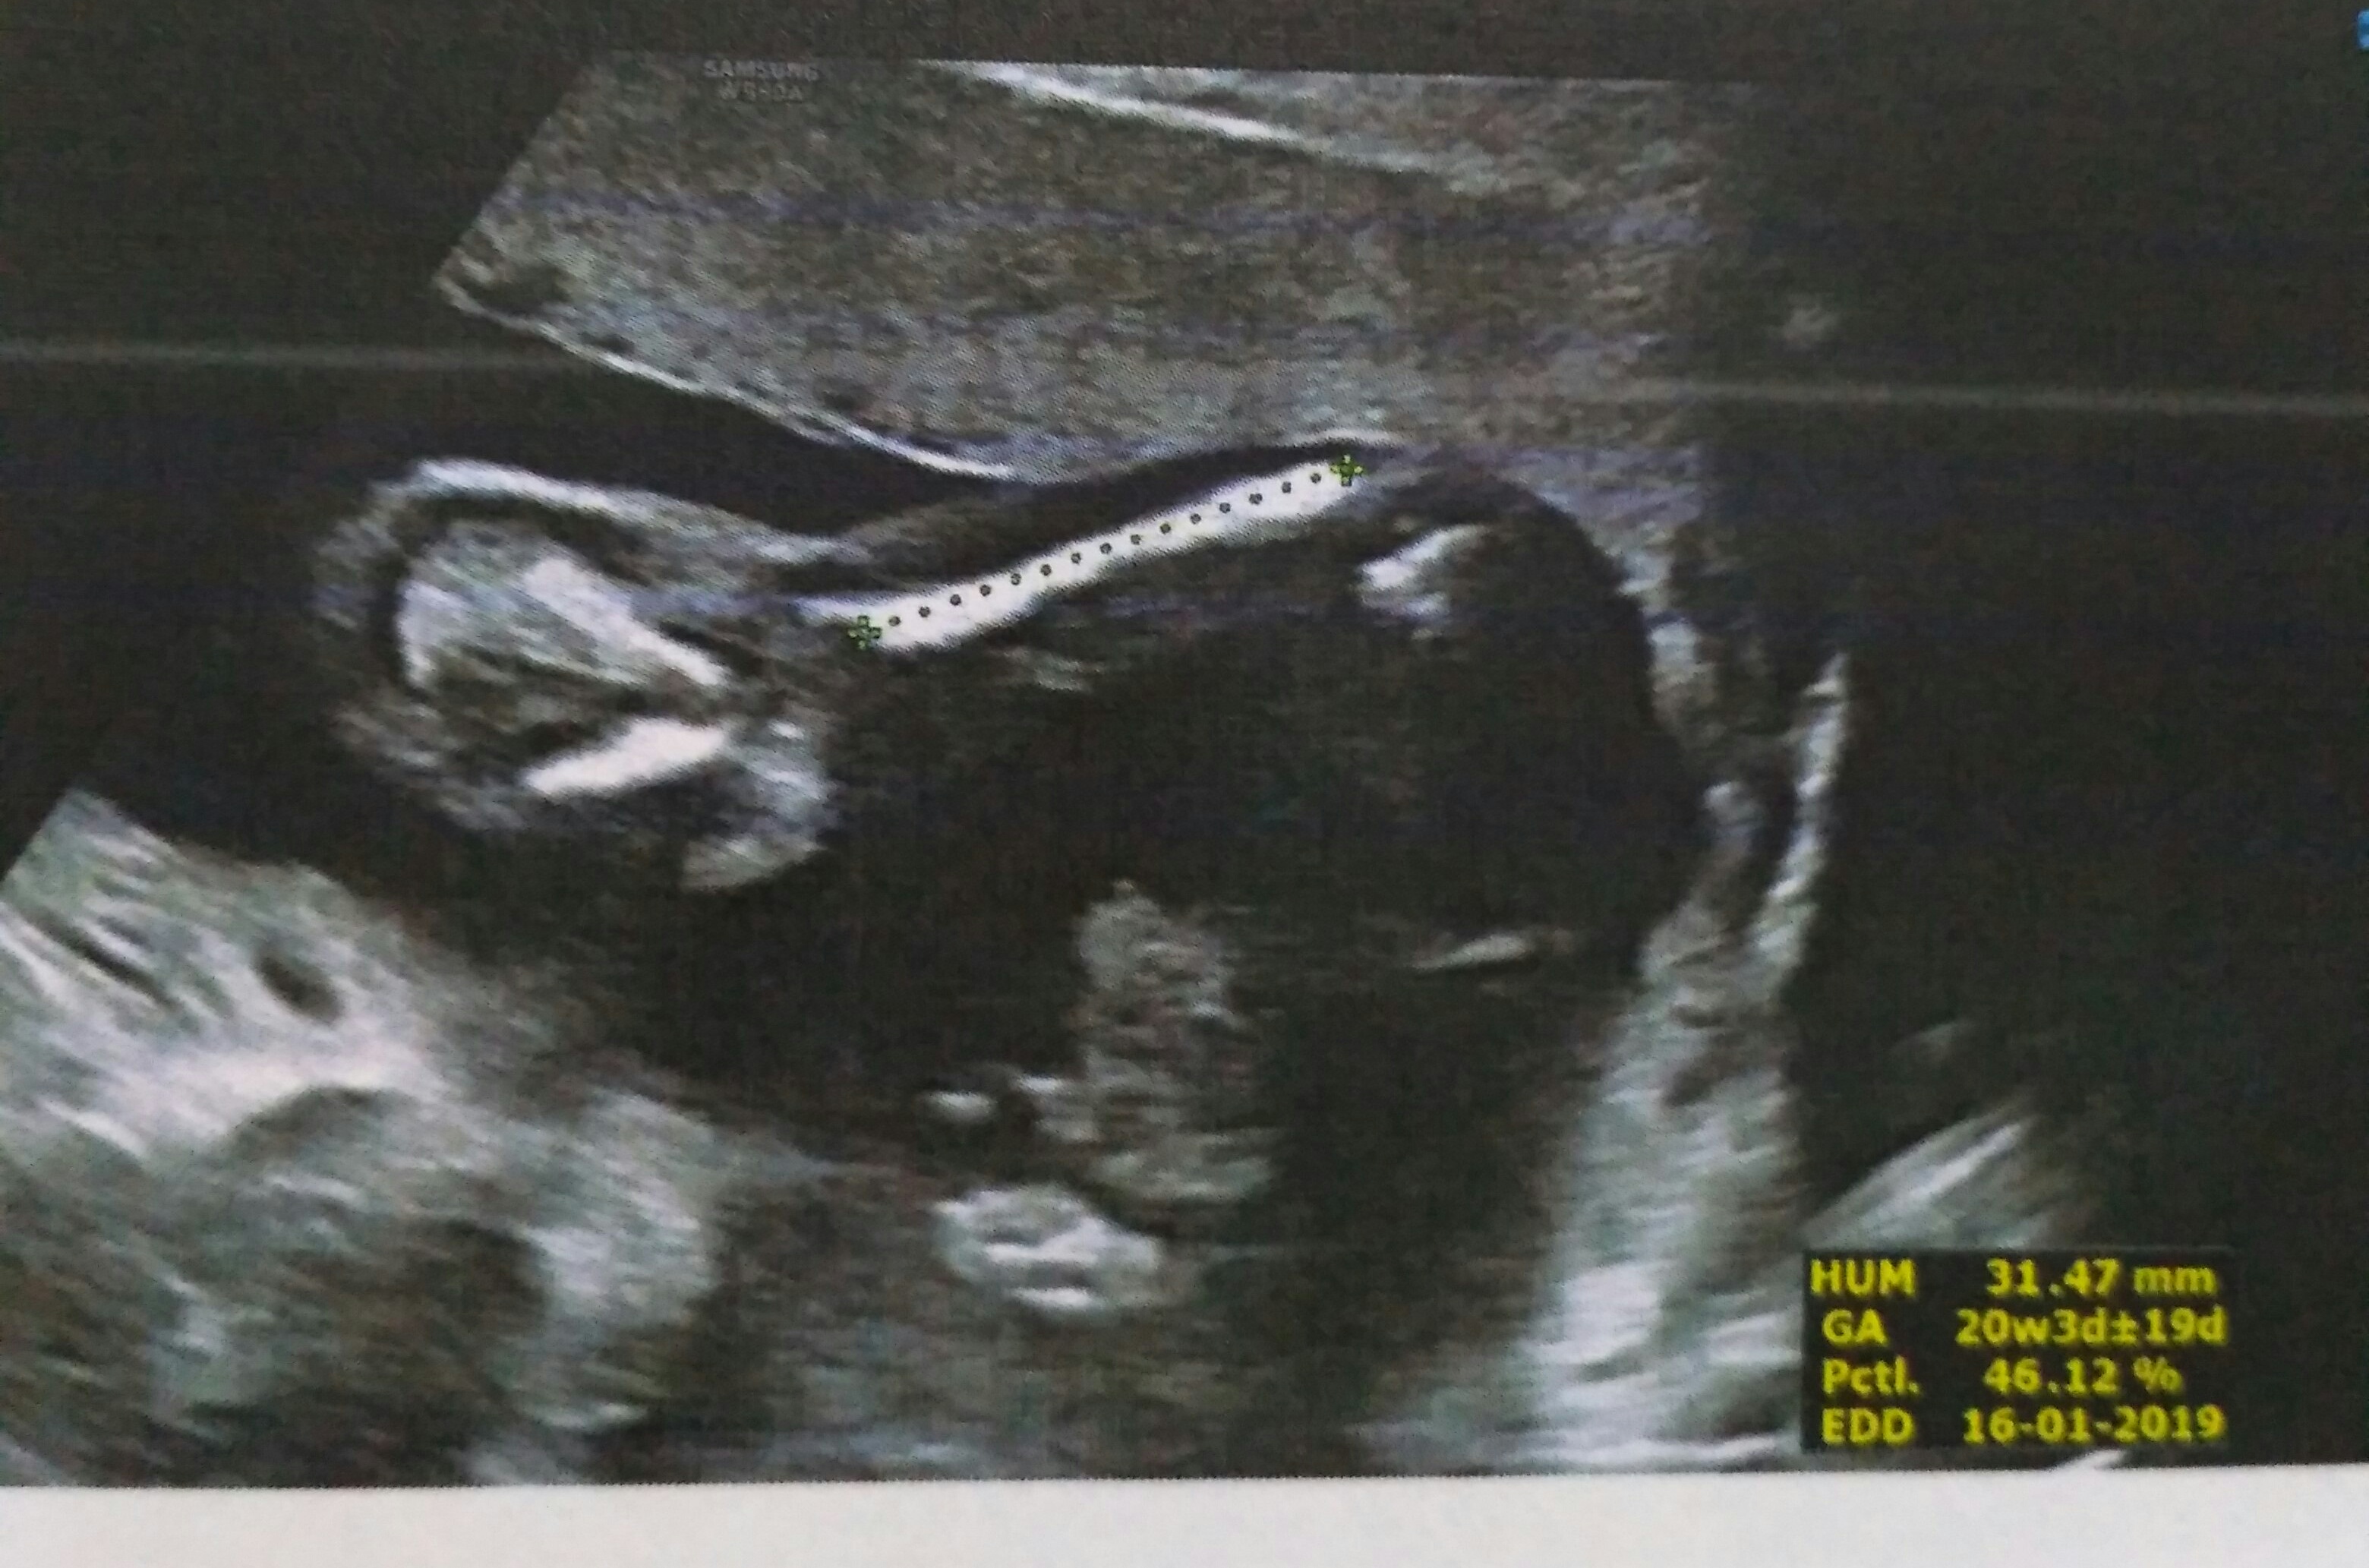

Another pic from the same scanAttachment 39880